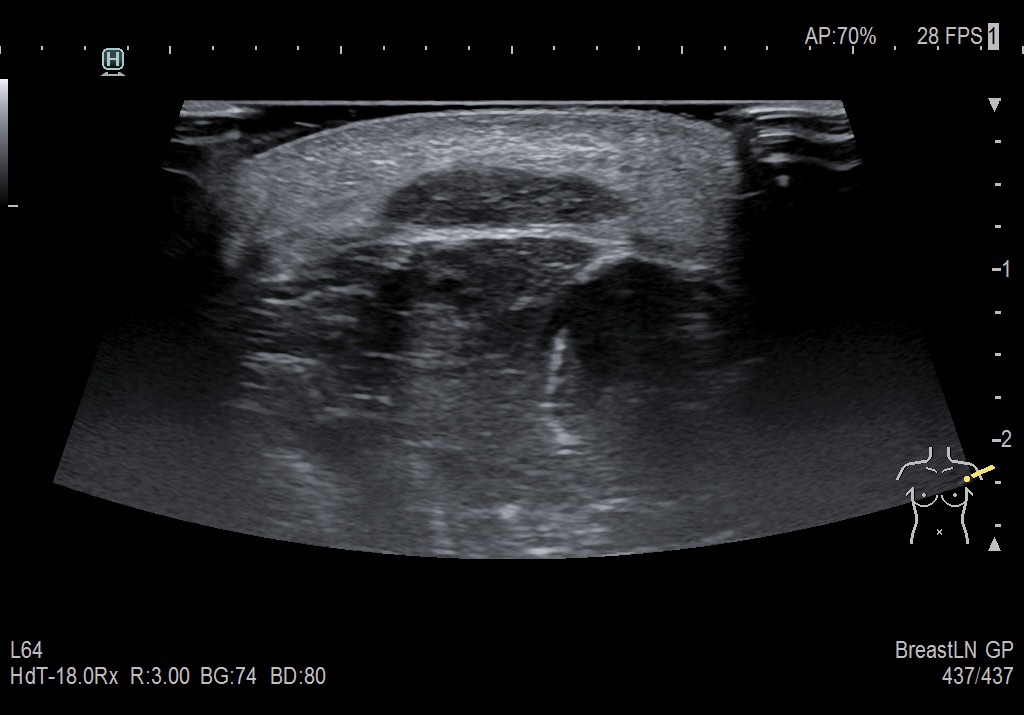

Finalmente, se le realizó una ecografía de la zona afectada, donde se observó una imagen ovalada, hipoecoica, sin signos de vascularidad. Inicialmente, esta imagen fue interpretada como un lipoma, dada su forma y apariencia. Sin embargo, tras revisar detalladamente la historia clínica de la paciente y conocer que el inicio de los síntomas ocurrió después de la vacunación, el radiólogo concluyó que era probable que este hallazgo se tratara de un efecto adverso causado por la inoculación de la vacuna.